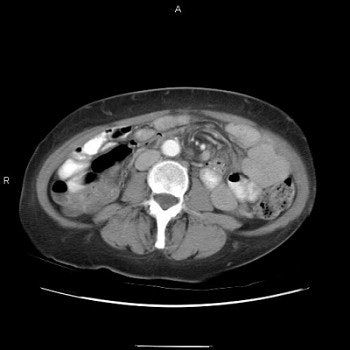

Both UGI and CT detect signs signaling adhesion or internal hernia, such as dilated bowel segments and a transition from dilated to collapsed bowel. But only CT depicts classic signs of internal hernia such as crowding, stretching, and engorgement of mesenteric vessels.

Three images show internal hernia following Roux-en-Y gastric bypass. The CT scans (top, middle) and small bowel study (below) show a cluster of mildly dilated bowel segments in the left abdomen, with a crowded, twisted appearance of the bowel and mesenteric vessels. Images courtesy of Dr. Michael Federle.